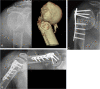

Background: The purpose of this study was to evaluate the role of medial support and clinical factors responsible on outcomes and major complications associated with treatment of unstable proximal humerus fractures using a locking plate and suture augmentation.

Methods: Sixty-three cases in 62 patients (42 female, 20 male) were evaluated between September 2004 and October 2008. Cases were divided into either a medial support group (36 cases) or non-medial support group (27 cases). Clinical and radiographic evaluations included Neer's evaluation criteria, the neck-shaft angle using the Paavolainen method, and complications. We analyzed the correlation between bone- and fracture- related complications and three independent clinical variables, such as the presence of medial support, fracture type, and osteoporosis by way of multivariate logistic regression.

Results: There were statistically significant differences in the overall incidence of complications based on the presence of medial support (p = 0.014) and preoperative fracture type (p = 0.018), but no differences based on the presence of osteoporosis (p = 0.157). According to multivariate logistic regression analysis, the restoration of medial support was the most reliable factor to prevent bone- and fracture- related complications. In addition, when we compared the incidence of bone- and fracture-related complications in the presence or absence of medial support among 30 patients with osteoporosis, the group with restoration of medial support had only one complication of humeral head osteonecrosis despite the presence of osteoporosis (5.9% vs. 46.2%, p = 0.025). According to Neer's criteria, excellent or satisfactory clinical results accounted for seventy-three percent of the total cases (46 of 63 cases). Seventy-eight percent (49 of 55 cases) showed good radiographic results by the Paavolainen method. There were 14 complications in 13 of 63 cases (20.6%).

Conclusions: In the treatment of unstable proximal humerus fractures with locking plate technology and suture augmentation, we suggest that obtaining medial support is an important factor in preventing major bone- and fracture-related postoperative complications such as reduction loss or nonunion.